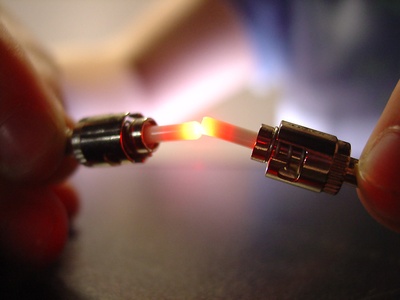

Pulse oximeter (NIR)

Pulse oximeters use two wavelengths—red and near-infrared around 0.66 and 0.94 µm—to measure blood oxygen saturation by comparing absorption. They’re small, clip-on devices used widely in hospitals, clinics, and home monitoring.